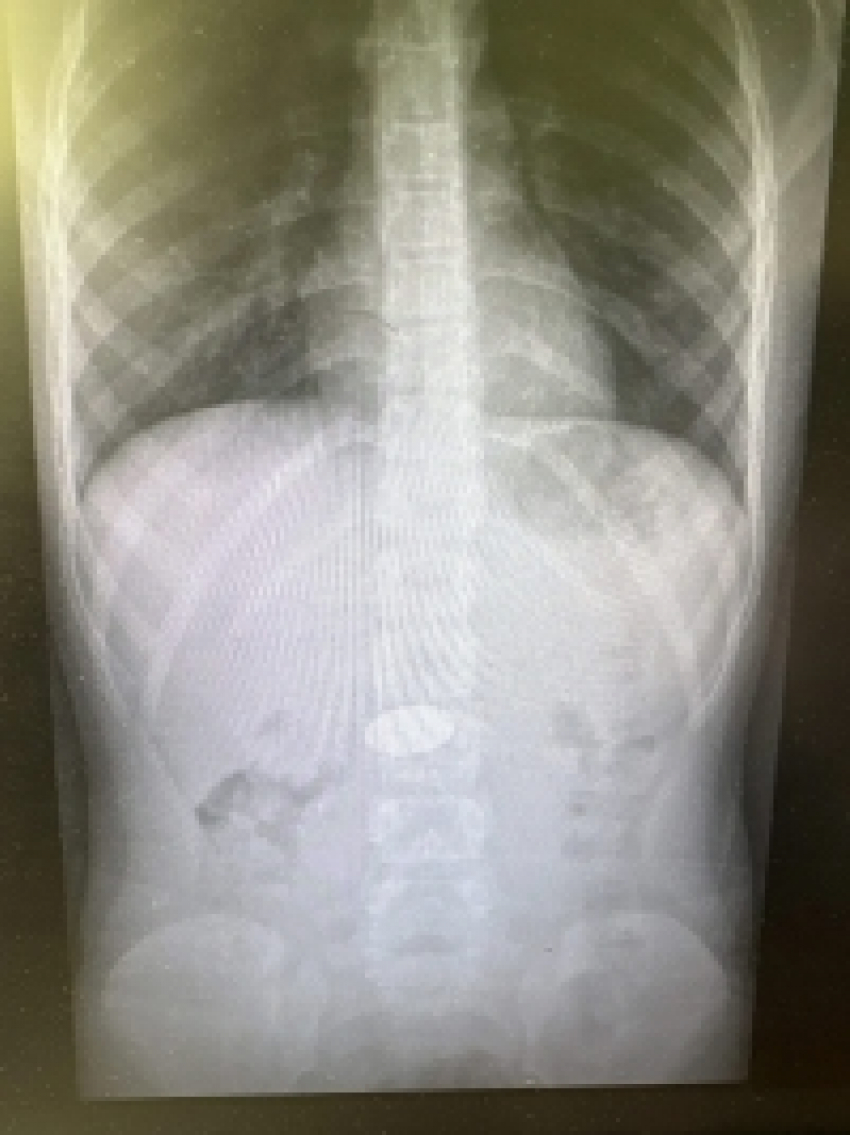

В детское хирургическое отделение клинической больницы №7 в Волгограде поступил ребенок младшего возраста. При проведении диагностического обследования врачи обнаружили в желудке малыша инородное тело — крупную 5-рублевую монету, которую, по недосмотру родителей, проглотил ребенок.

Фото: сайт Облздрава